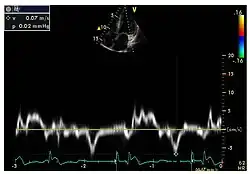

Die linksventrikulären strukturellen Veränderungen des Herzens finden sich bei Morbus-Fabry-Patienten häufig. Mittels Echokardiografie (Ultraschalluntersuchung des Herzens) oder kardialer Magnetresonanztomographie (MRT) können die meist konzentrischen Hypertrophien[80][81] sichtbar gemacht werden. Da mit zunehmendem Alter durch die Ersatzfibrose die linksventrikuläre Hinterwand des Herzens immer dünner wird, ist die Messung der Septumdicke – das ist die Stärke der Scheidewand zwischen linker und rechter Herzhälfte – besonders wichtig. Unabhängig von den strukturellen Veränderungen scheint die Systole, die Phase, in der das Blut aus der linken und rechten Herzkammer herausgepresst wird, bei der Messung mit konventionellen Methoden weitgehend erhalten zu bleiben.[80][81][82][91] Die durch Morbus Fabry verursachte Kardiomyopathie ist durch eine reduzierte Kontraktion und Relaxation des Herzmuskels gekennzeichnet. Gewebedoppler (sowohl tissue velocity imaging als auch strain rate imaging) kann die Herzmuskelfunktion quantifizieren.[7][92] Mit dieser Methode kann die Kardiomyopathie noch vor der Entwicklung einer linksventrikulären Hypertrophie diagnostiziert werden.[91][93]

- Echokardiografien von Patienten mit Morbus Fabry

-

Parasternale lange Achse: Deutlich sichtbar die linksventrikuläre Hypertrophie mit erhöhter Septumdicke. -

Parasternale kurze Achse: Die Aufnahme zeigt ebenfalls eine linksventrikuläre Hypertrophie. -

Gewebedoppler-Echokardiographie des Mitralanulus (Mitralring) mit nahezu normaler systolischer Funktion